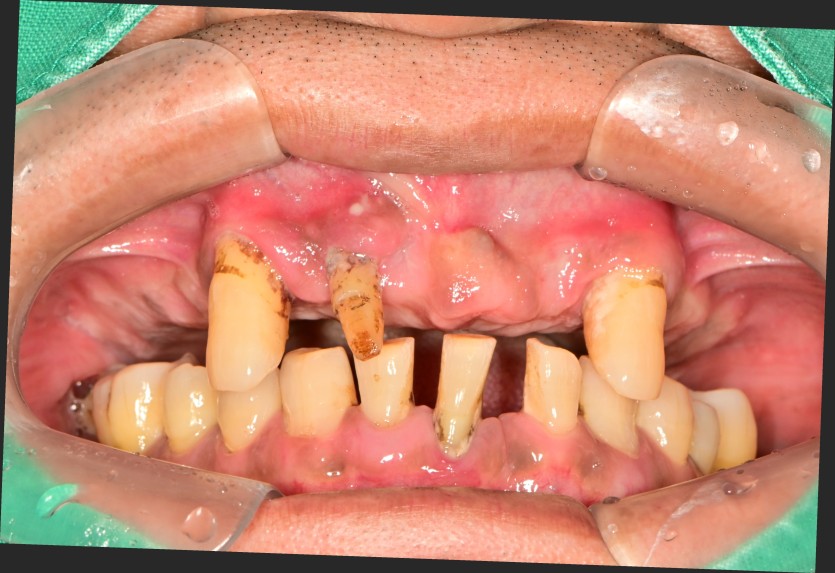

만 57세 전체 임플란트 증례입니다.(하악 일부)

15개의 임플란트로 완성하였습니다.